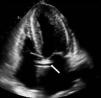

Mulher de 67 anos, com antecedentes de esclerodermia e hipertensão arterial, sem sintomas cardíacos prévios, foi internada para avaliação do envolvimento sistémico da esclerodermia. Ao exame objetivo apresentava um sopro sistólico no apex grau ii/vi. O eletrocardiograma revelou ritmo sinusal e bloqueio fascicular anterior esquerdo. O ecocardiograma mostrou na incidência para-esternal esquerda eixo longo uma imagem tubular anómala em continuidade com a parede anterior da aorta ascendente (Figura 1). Em para-esternal eixo curto a nível da aorta é visível a mesma estrutura tubular circundando a aorta (Figura 2). Em apical quatro câmaras observou-se a imagem tubular com 2mm de diâmetro com 42mm de comprimento, transversal ao septo interauricular. Não foram identificados a origem e o fim da estrutura. Com Doppler de cor observou-se fluxo no seu interior (Figuras 3 e 4). Pelo facto de se suspeitar de uma estrutura vascular, realizou-se cateterismo cardíaco, que revelou uma origem anómala da artéria coronária esquerda (ACE) a partir do segmento proximal da coronária direita com trajeto epicárdico e anterior à aorta (Figura 5). Os achados ecocardiográficos mais associados à esclerodermia são a hipertensão pulmonar e o envolvimento pericárdico incluindo a pericardite fibrinosa. Não há casos descritos da associação entre esclerodermia e origem anómala das artérias coronárias, pelo que este caso poder-se-á tratar de uma coincidência. A origem da ACE a partir do óstio da coronária direita ocorre em apenas 0,15%1 da população, estando associada a morte súbita2.